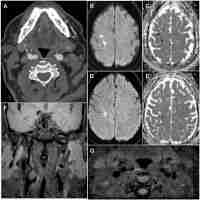

| Description | Atheromatous disease is the first cause of death and dependency in developed countries and carotid artery atherosclerosis is one of the main causes of severe ischaemic strokes. Current management strategies are mainly based on the degree of stenosis and patient selection has limited accuracy. This information could be complemented by the identification of biomarkers of plaque vulnerability, which would permit patients at greater and lesser risk of stroke to be distinguished, thus enabling a better selection of patients for surgical or intensive medical treatment. Although several circulating protein-based biomarkers with significance for both the diagnosis of carotid artery disease and its prognosis have been identified, at present, none have been clinically implemented. This review focuses especially on the most relevant clinical parameters to take into account in routine clinical practice and summarises the most up-to-date data on epigenetic biomarkers of carotid atherosclerosis and plaque vulnerability. |